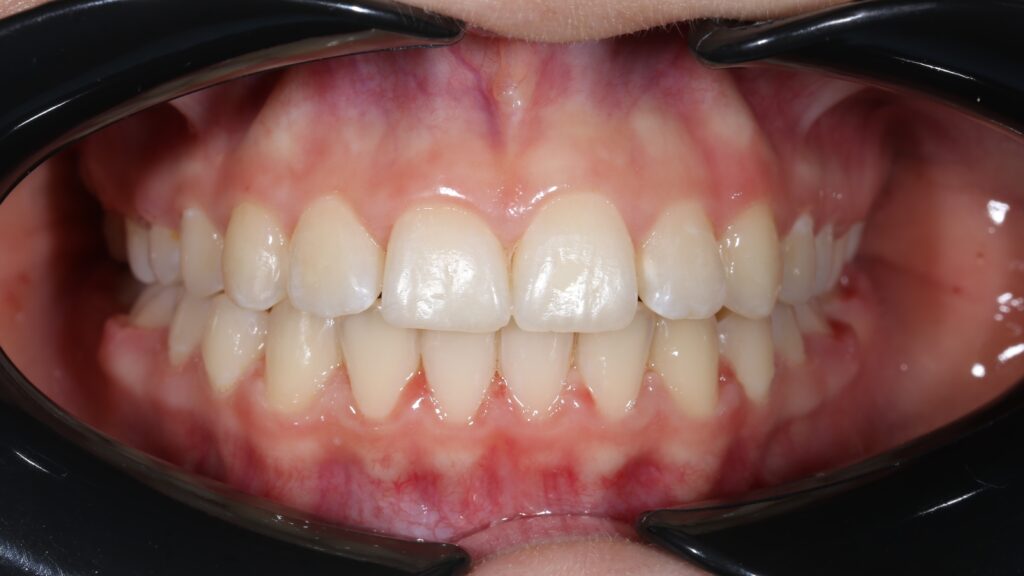

пациент после ортодонтического лечения